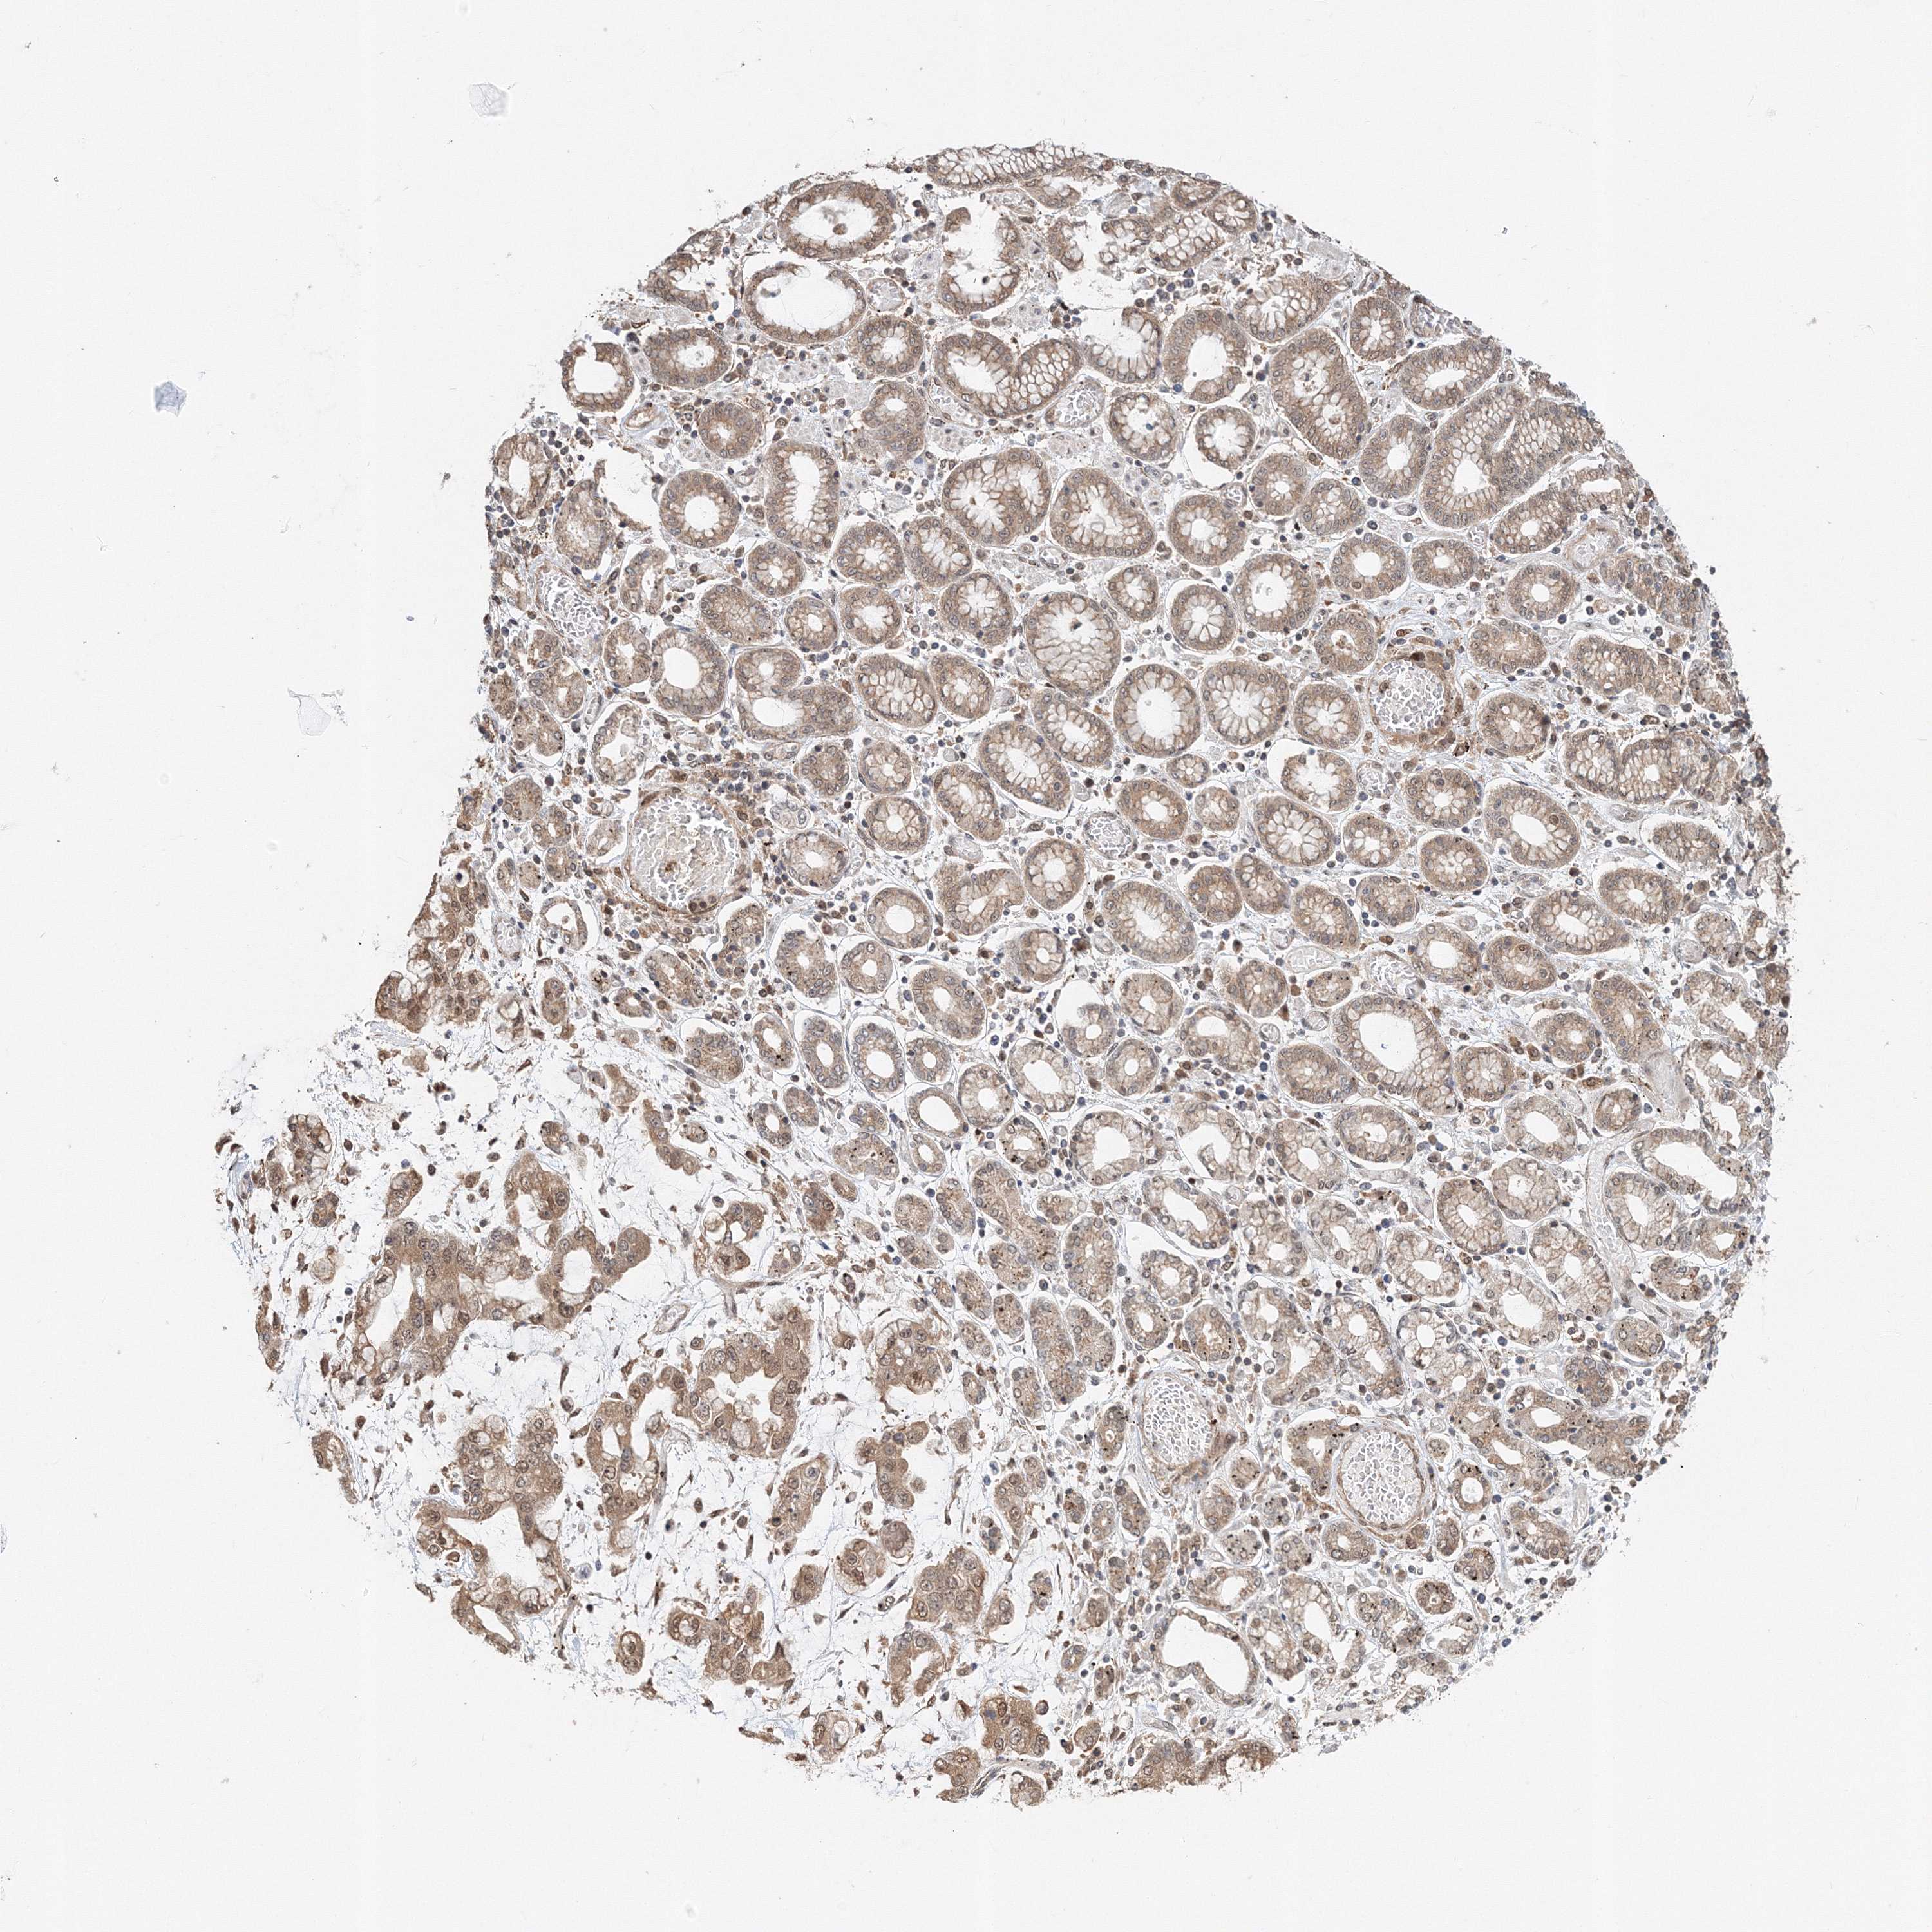

STOMACH CANCER - Protein expressioni

A mouse-over function shows sample information and annotation data. Click on an image to view it in a full screen mode. Samples can be filtered based on level of antibody staining by selecting one or several of the following categories: high, medium, low and not detected. The assay and annotation is described here.

Note that samples used for immunohistochemistry by the Human Protein Atlas do not correspond to samples in the TCGA dataset.

Antibody stainingi

Antibody staining in the annotated cell types in the current human tissue is reported as not detected, low, medium, or high, based on conventional immunohistochemistry profiling in selected tissues. This score is based on the combination of the staining intensity and fraction of stained cells.

Each image is clickable and will lead to virtual microscopy that enables deeper exploration of all samples and also displays staining intensity scores, fraction scores and subcellular localization as well as patient and tissue information for each sample.

Antibody HPA036921

Antibody HPA036922

Staining

High

Medium

Low

Not detected

Intensity

Strong

Moderate

Weak

Negative

Quantity

>75%

75%-25%

<25%

None

Location

Nuclear

Cytoplasmic/membranous

Cytoplasmic/membranous,nuclear

Adenocarcinoma, NOS